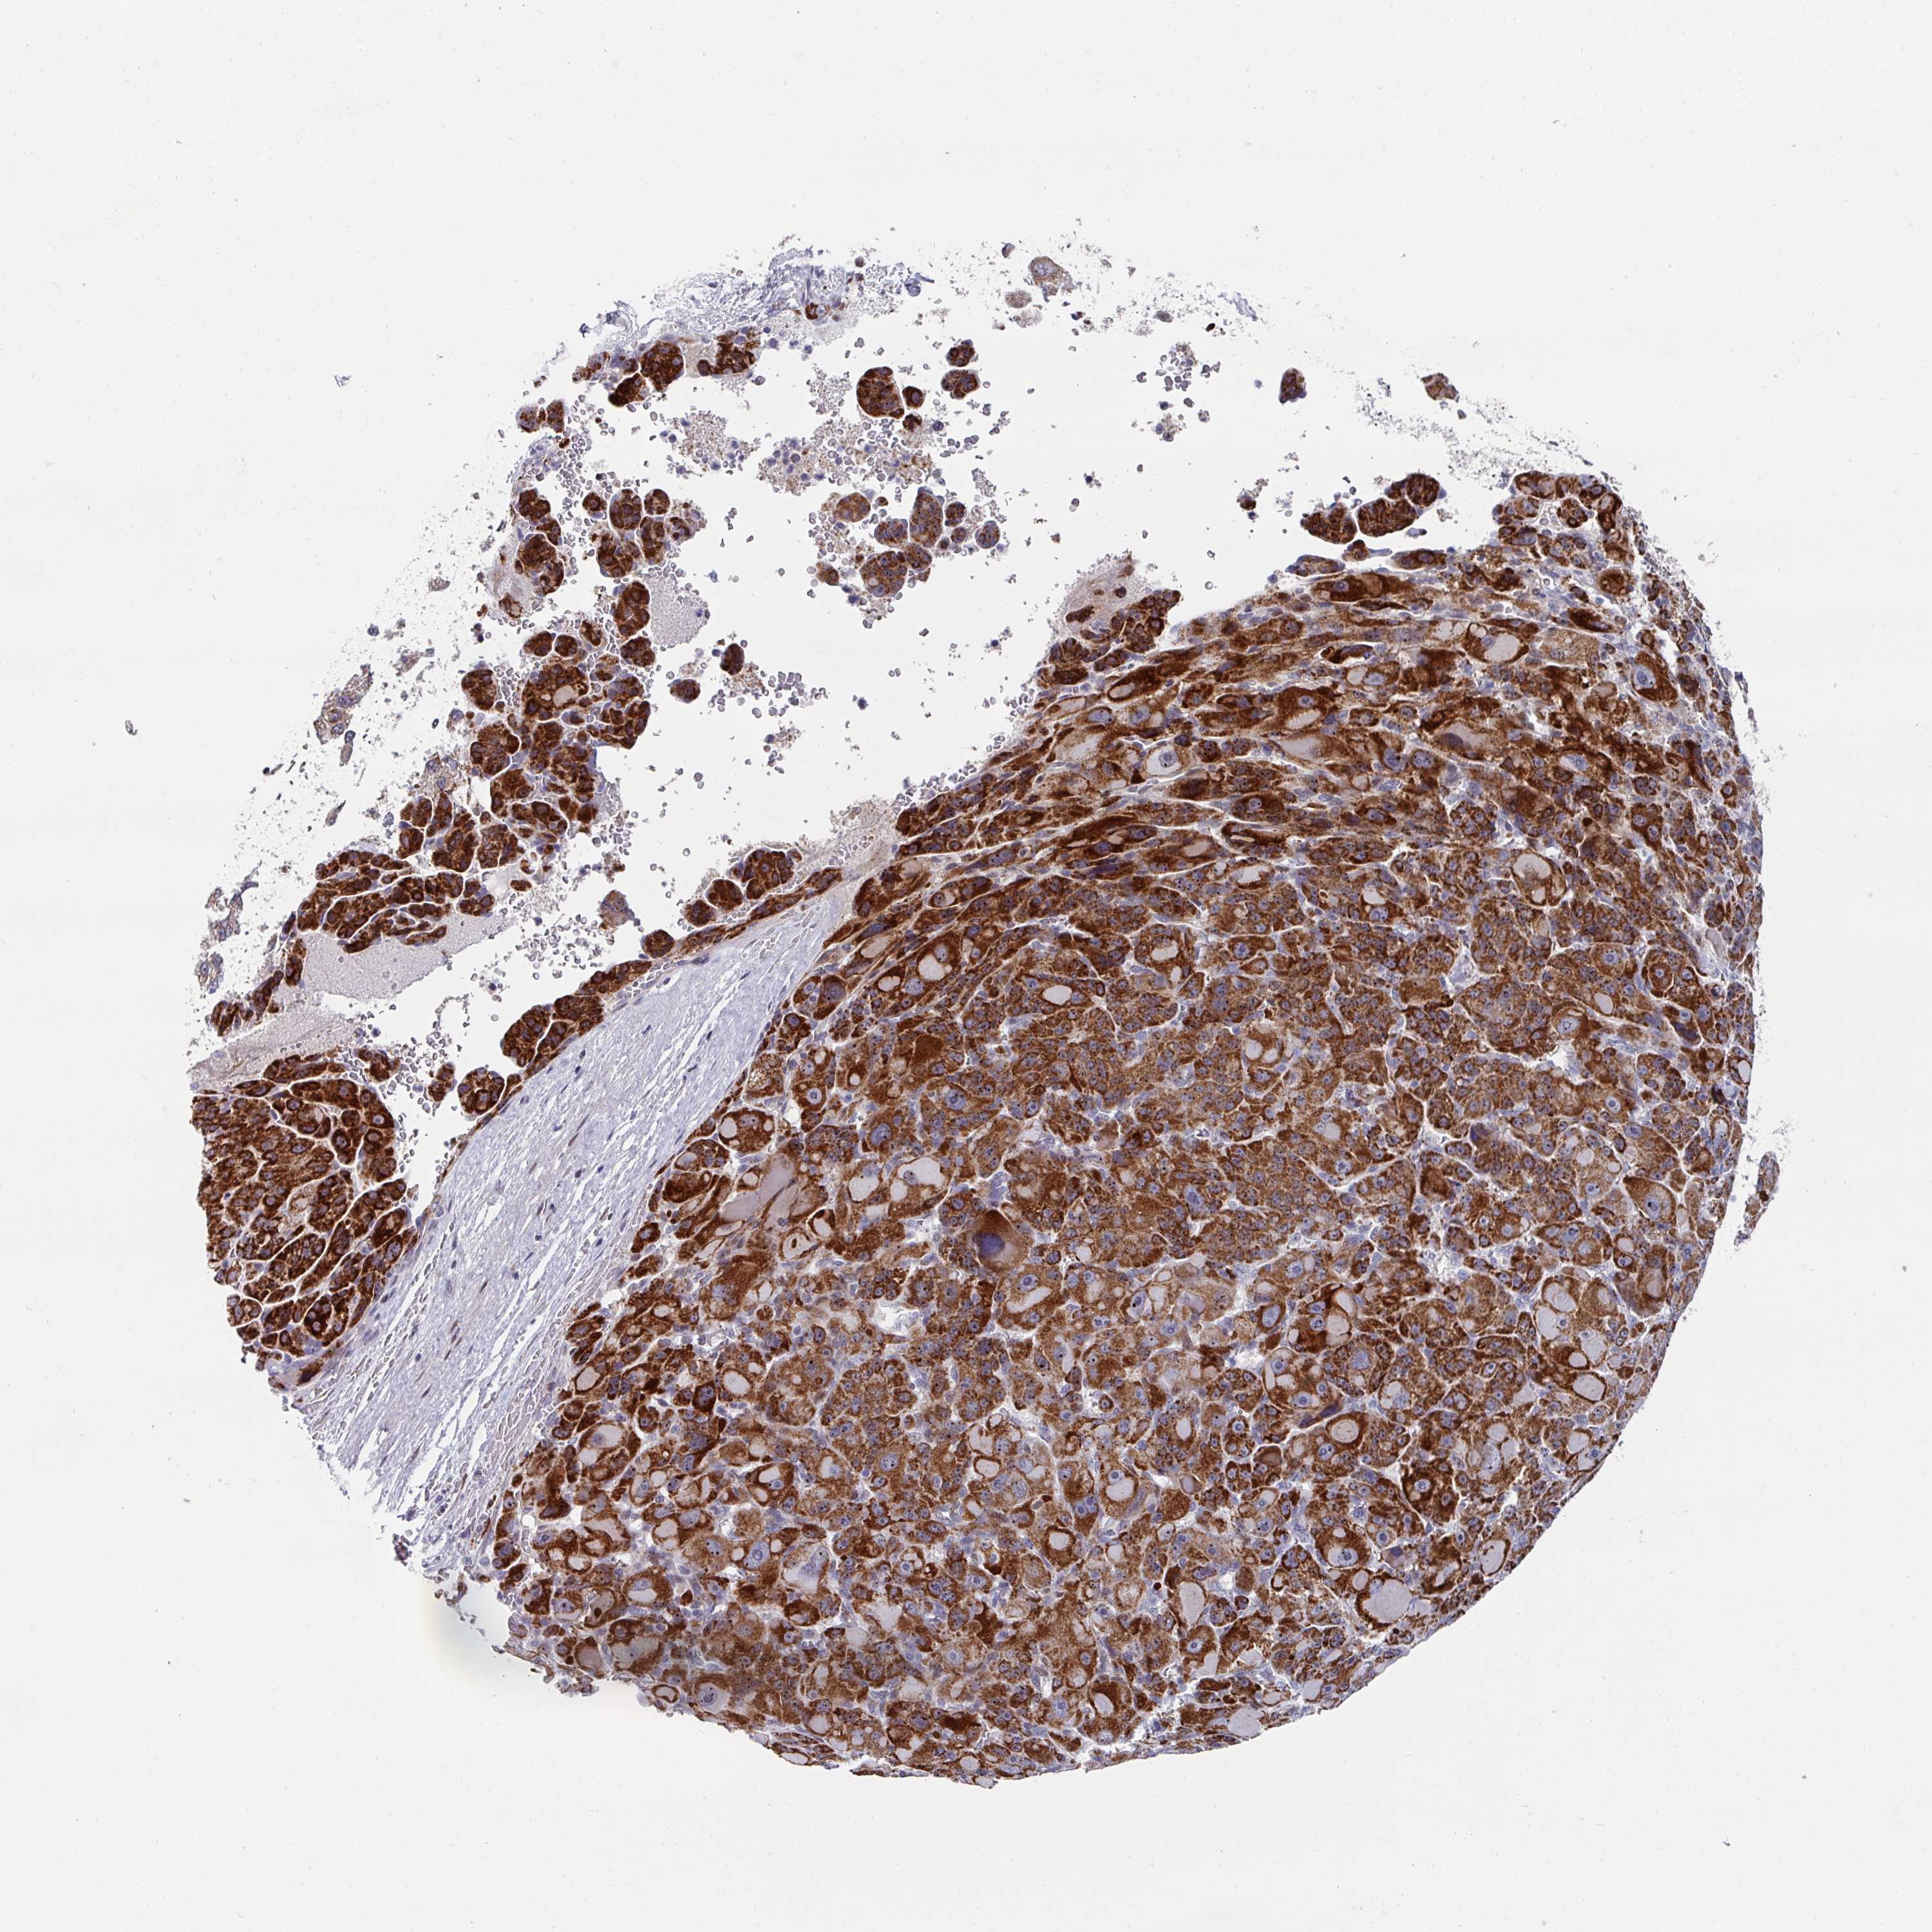

LIVER CANCER - Protein expressioni

A mouse-over function shows sample information and annotation data. Click on an image to view it in a full screen mode. Samples can be filtered based on level of antibody staining by selecting one or several of the following categories: high, medium, low and not detected. The assay and annotation is described here.

Note that samples used for immunohistochemistry by the Human Protein Atlas do not correspond to samples in the TCGA dataset.

Antibody stainingi

Antibody staining in the annotated cell types in the current human tissue is reported as not detected, low, medium, or high, based on conventional immunohistochemistry profiling in selected tissues. This score is based on the combination of the staining intensity and fraction of stained cells.

Each image is clickable and will lead to virtual microscopy that enables deeper exploration of all samples and also displays staining intensity scores, fraction scores and subcellular localization as well as patient and tissue information for each sample.

Antibody HPA048677

Antibody HPA056480

Antibody CAB011574

Staining

High

Medium

Low

Not detected

Intensity

Strong

Moderate

Weak

Negative

Quantity

>75%

75%-25%

<25%

None

Location

Nuclear

Cytoplasmic/membranous

Cytoplasmic/membranous,nuclear

Carcinoma, Hepatocellular, NOS